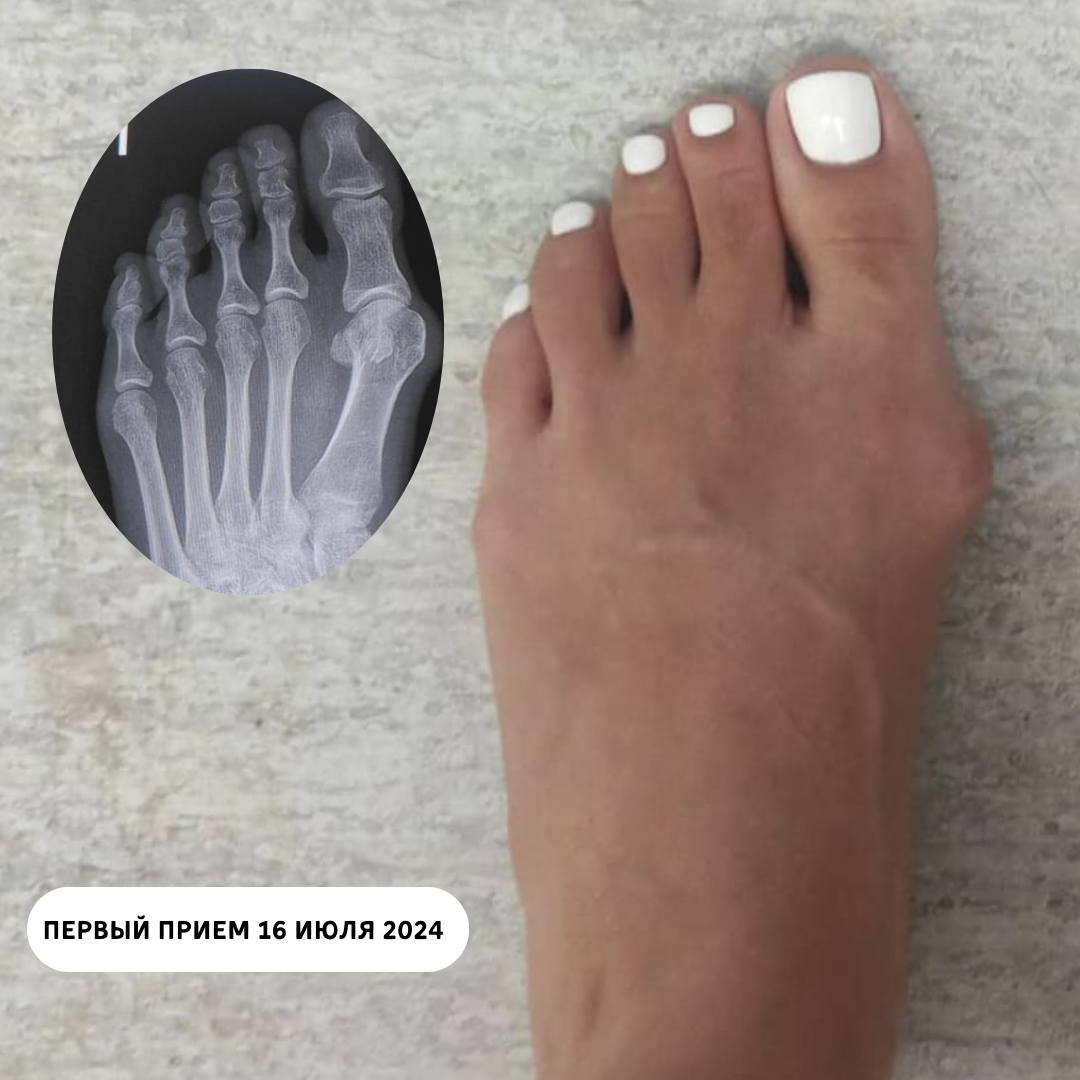

Пациентка 33 лет обратилась в июле 2024 с жалобами на боль при ходьбе в области первого плюснефалангового сустава, трудности в подборе обуви.

На осмотре объем движений в суставе в полном объеме, а на рентгенограммах - вывих первого пальца стопы.

Выставлен настоящий диагноз: Вальгусная деформация первого плюсне-фалангового сустава.

Из истории болезни выяснилось, что попытки лечения стельками и межпальцевыми распорками оказались безуспешными.

Первый прием